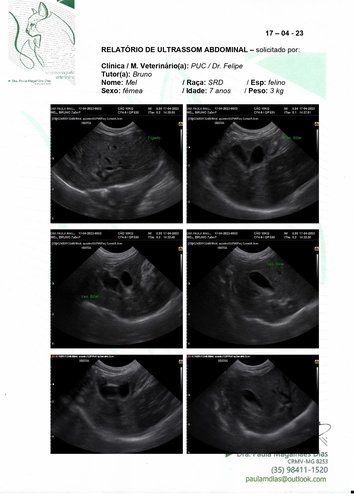

Olá, meu nome é Mel tenho 7 aninhos e peso 3kg (sim, sou bem pequinininha pra minha idade e comparado ao meu irmão de ninhada). Eu e meu maninho Cheetos fomos adotados pelo meu papai Bruno quando nossa antiga tutora faleceu. Nós ja tinhamos 2 aninhos na época, e nunca degrudamos um do outro nesses anos todos. Desde quando meu papai nos acolheu tínhamos que ficar separado da nossa irmã mais velha porque eu sempre fiz meu xixizinho em todo lugar que eu vejo, não faço na caixa de areia e nem mesmo cubro quando decido fazer lá. Mas nunca faltou carinho e amor independente de tudo. Recentemente papai e mamãe decidiram me levar no veterinario para ver o que seria esse problema de xixi em todo lugar, o doutor pediu ultrassom e infelizmente descobrimos a princípio um tumor bem grande perto da bexiga (o qual poderia ter deslocado minha bexiguinha e talvez possa explicar algumas coisas). O doutor disse que teríamos que fazer uma tomografia em outro estado pois onde moramos não tem, e pelas contas dos meus papais ia ficar mais de R$2000,00 fora a cirurgia ><. Mas o doutor disse que podemos ir direto pra cirurgia pra tentar solucionar e não alastrar mais o tumor. Quando chegamos para a cirurgia nao pude fazer por ter fugido do jejum porem me pediram pra refazer os exames e nisso apareceu que o que era um tumor parecia mais uma castração mal feita que tinha deixado partes do ovario e tava causando infecções. Meus papais vieram pedir ajuda pois a cirurgia vai ficar cara fora os medicamentos.

Vamos anexar aqui todas fotos, exame e valor da cirurgia! Qualquer ajuda é bem vinda e contamos com vocês pra logo logo eu ficar bem de novo e poder ficar grudada brincando com meus irmãozinhos!! <3